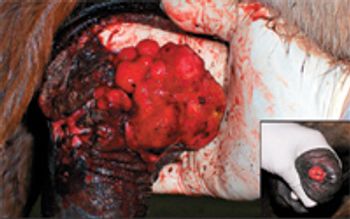

Pythiosis is notorious for being difficult to remove with surgery alone. "Usually that's the case because complete surgical excision without damaging vital anatomical structures is often not practical in the locations that this organism likes to establish infection," says Mathew P. Gerard, BVSc, PhD, Dipl. ACVS, clinical professor of equine surgery at North Carolina State University. "The main point about surgery for pythiosis is that it has to be radical excision if you're going to be successful. Wide surgical margins of at least 2 cm are recommended."